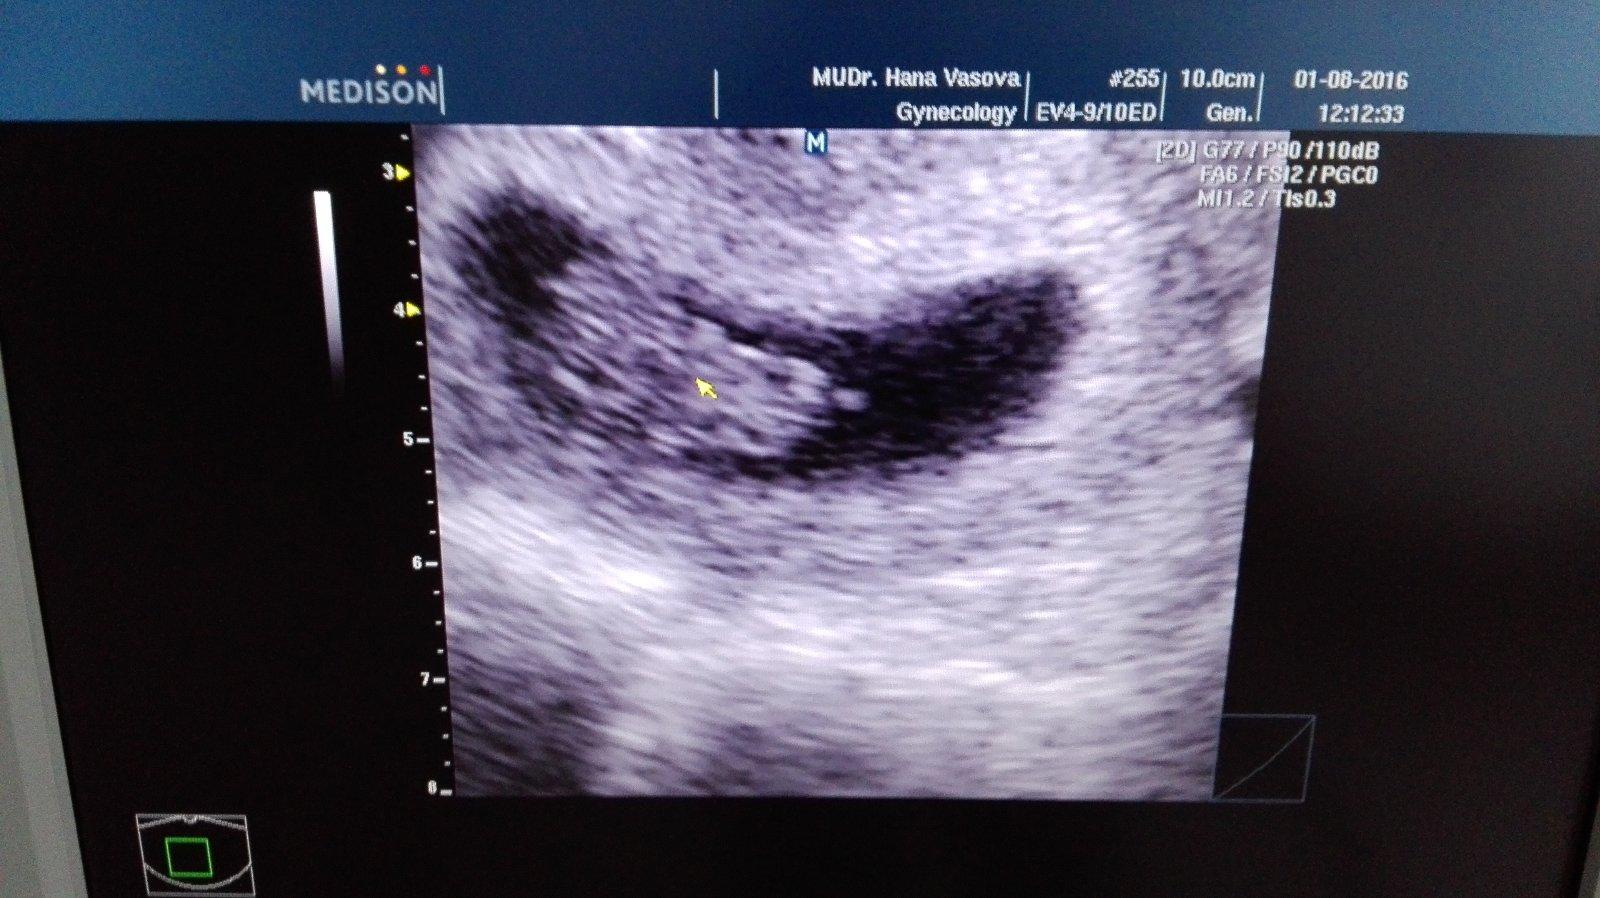

ahojte...dnes som bola na kontrolne sono...maternica cista...kyretaz nebude potrebna